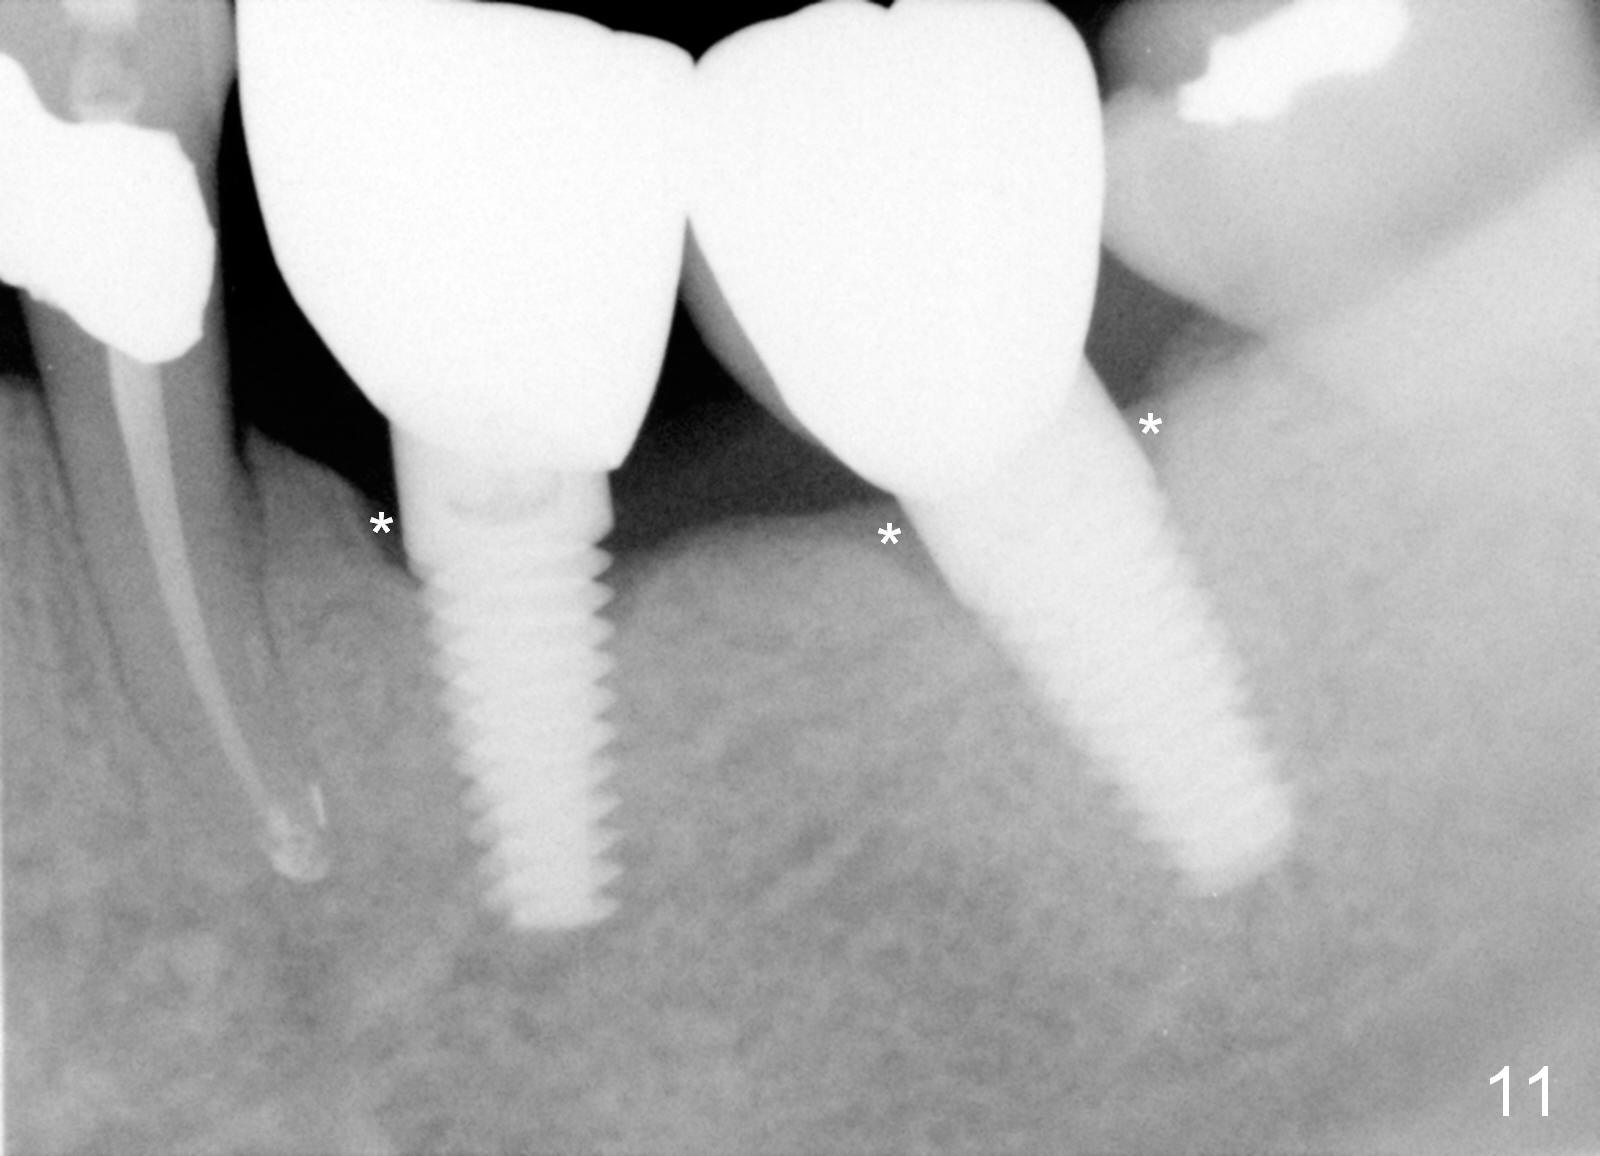

Three months postop, crestal bone has started to resorb (Fig.9 arrowheads). Resorption gets worse over time (Fig.10: 4 months post cementation, 11 months postop) (Fig.11: 1 year 2 month post cementation). On the other side (#30), postop bone resorption is not so severe. The patient's main concern is that she does not have normal taste ever since she got the implants.